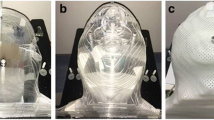

An anthropomorphic skull phantom was scanned using a 1.5‑T MR scanner, and the magnitude of MR distortion was calculated with (MRDR-DC and MRRT-DC) and without (MRDR-nDC and MRRT-nDC) distortion-correction algorithms. Automated noncoplanar volumetric modulated arc therapy (HyperArc, HA; Varian Medical Systems, Palo Alto, CA, USA) plans were generated for 53 patients with 186 brain metastases. The MR distortion at each gross tumor volume (GTV) was calculated using the distance between the center of the GTV and the MR image isocenter (MIC) and the quadratic regression curve derived from the phantom study (MRRT-DC and MRRT-nDC). Subsequently, the radiation isocenter of the HA plans was shifted according to the MR distortion at each GTV (HADC and HAnDC).